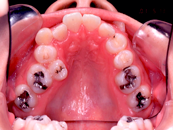

叢生 治療前 上顎

この患者さんでは、上下左右の歯を計4本抜きましたが、それでももスペースが足りませんので、さらに顎の形を変えて並べ替えました。

抜歯する歯は、変なところに生えていた犬歯ではなく、4番目の歯(=第一小臼歯)です。犬歯を抜くと、顎運動や歯並びの見た目、口元のふくらみがなくなることで老けて見えるなど、いろいろな悪影響があります。従って、できるだけ抜歯は避けたいのです。

歯を抜いたスペースを利用して、残りの歯をきれいに並べ替えてゆきます。この患者さんの場合は、抜いたスペースはほとんど余りませんので、意外に早く治療が終わりました。